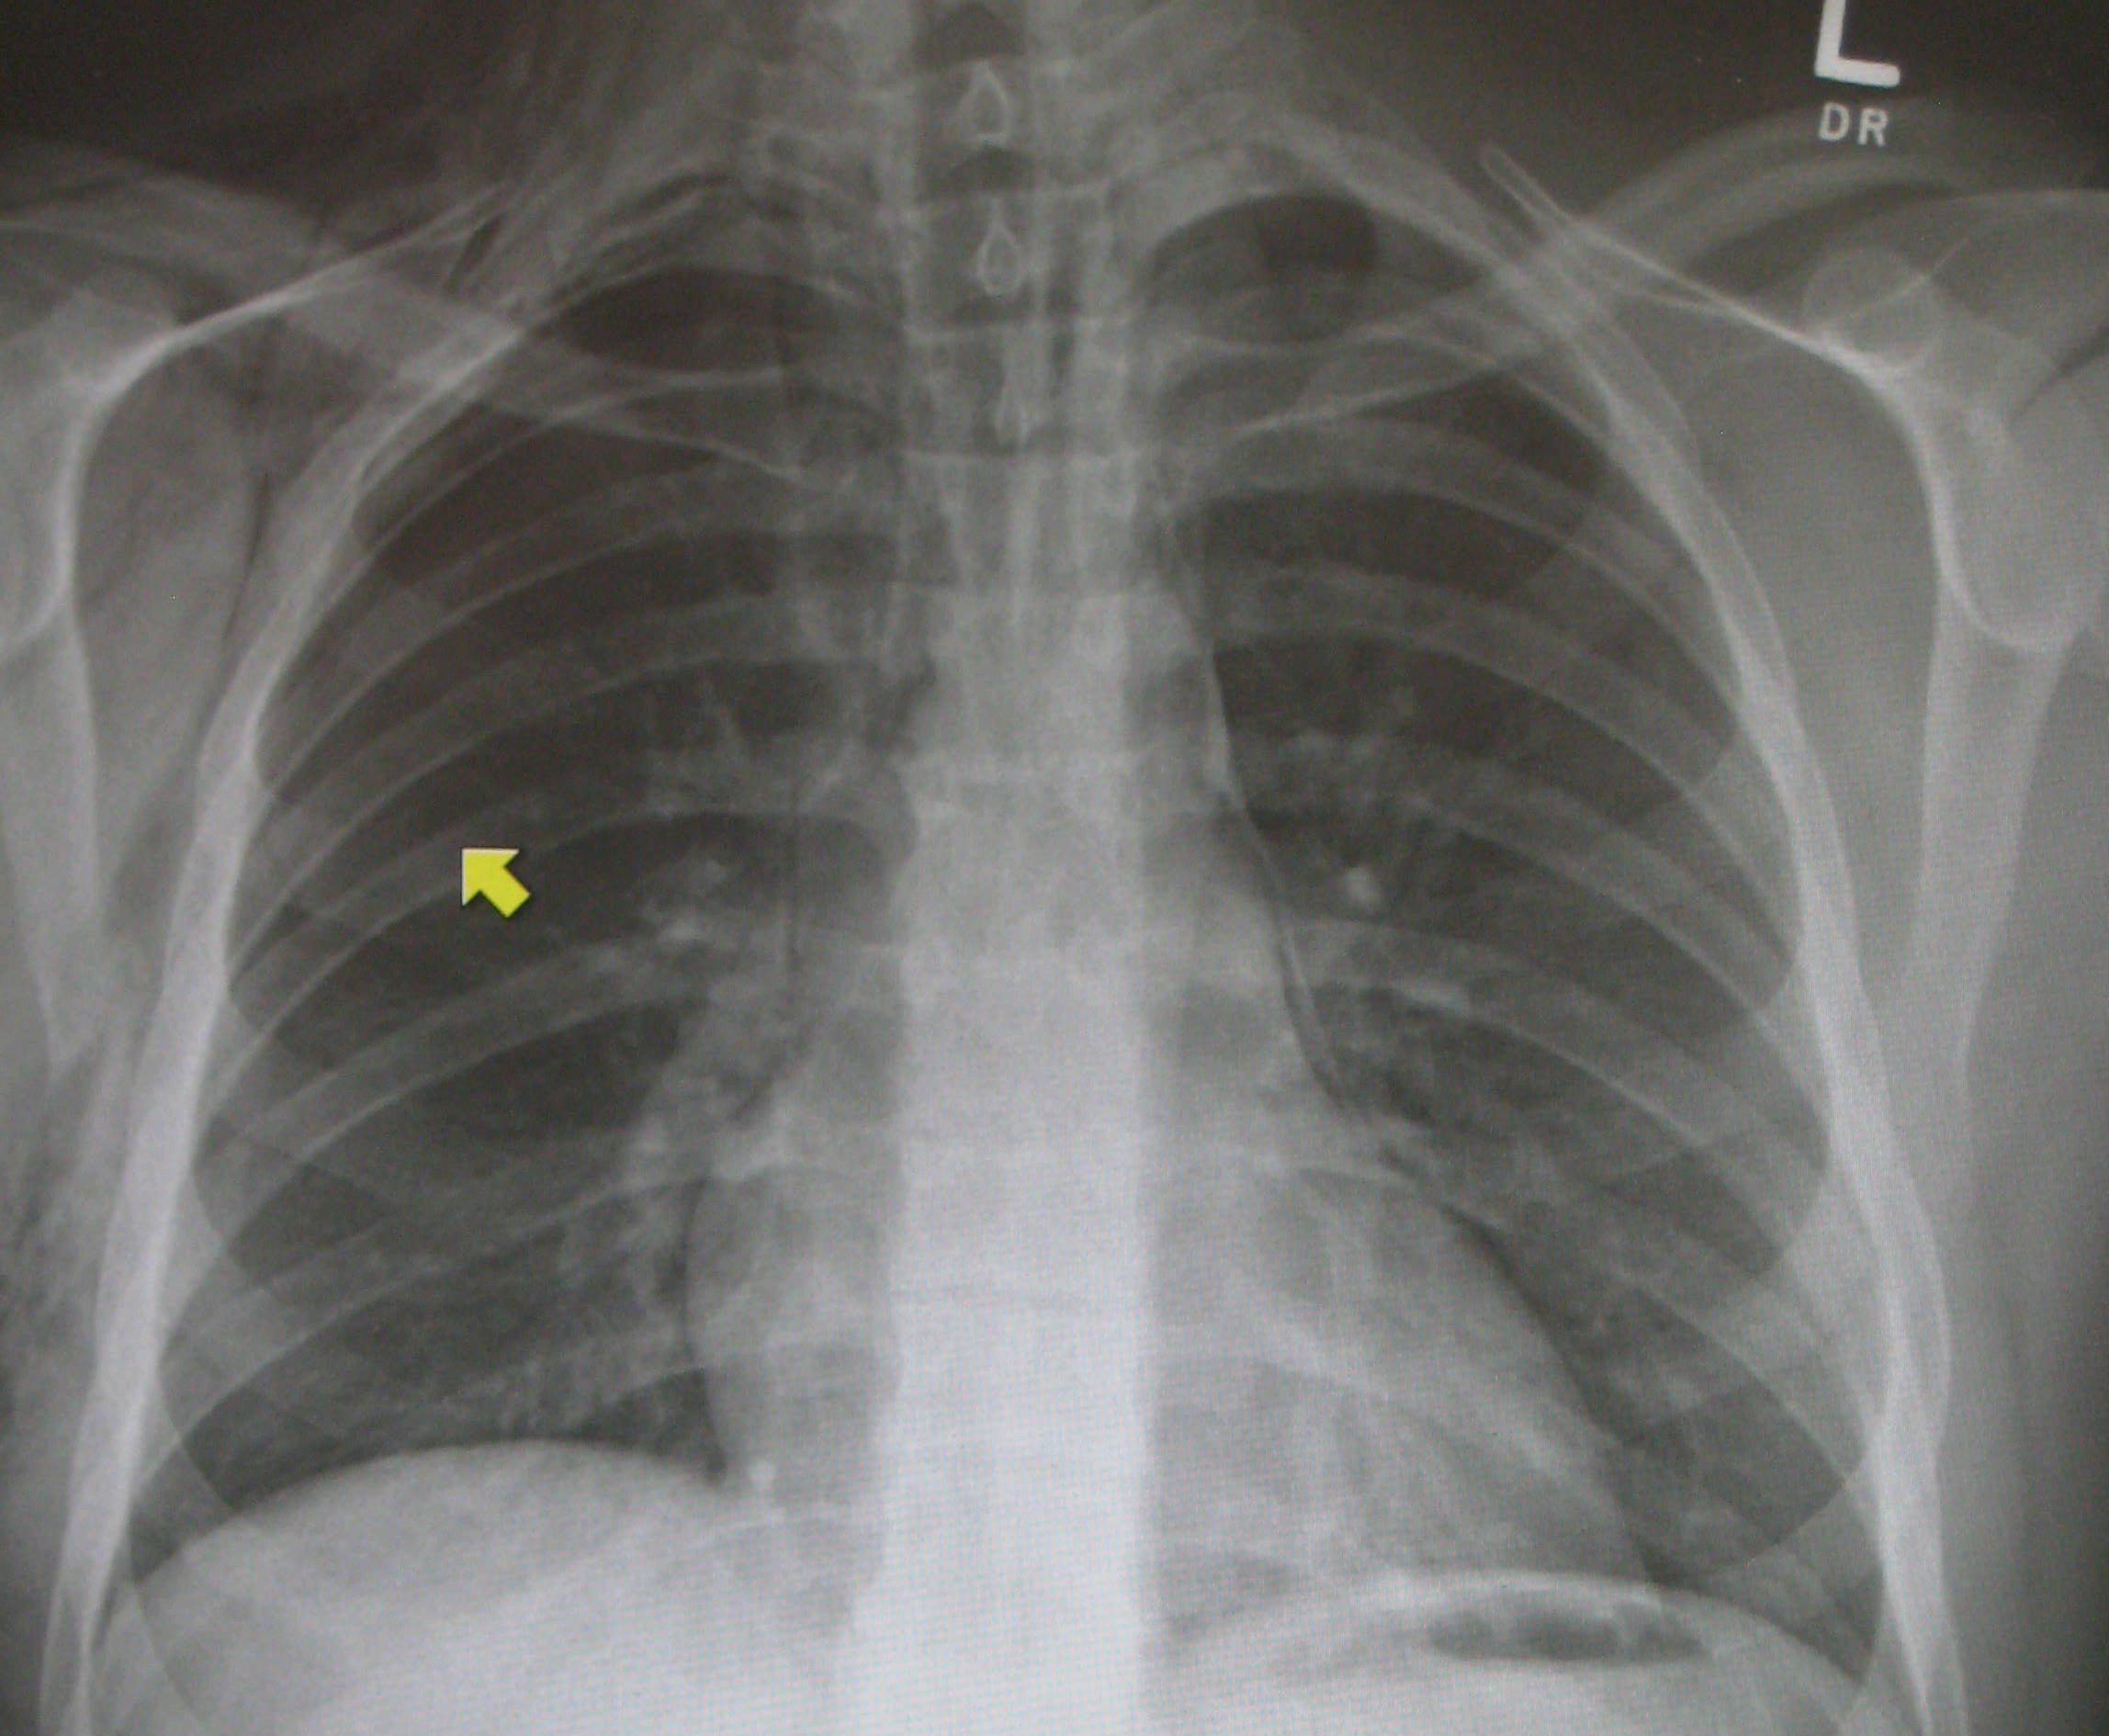

肋骨骨折一般有横型骨折,斜型骨折,螺旋型骨折,三小时后患者呼吸困难,用手捂住骨折处才能敢慢慢呼吸,呼吸有骨擦音,大小便都会疼痛,走路不能直腰,向患侧倾斜身体。